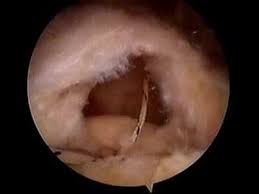

ארטרוסקופיה של הכתף